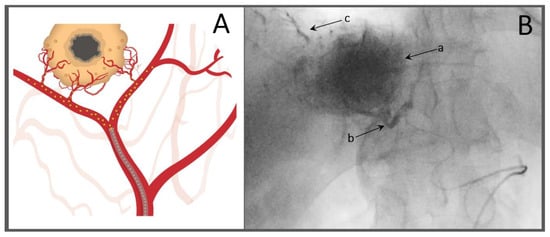

- Iwai, K.; Maeda, H.; Konno, T. Use of oily contrast medium for selective drug targeting to tumor: Enhanced therapeutic effect and X-ray image. Cancer Res. 1984, 44, 2115–2121. [Google Scholar] [PubMed]

- Kan, Z.; Sato, M.; Ivancev, K.; Uchida, B.; Hedgpeth, P.; Lunderquist, A.; Rosch, J.; Yamada, R. Distribution and effect of iodized poppyseed oil in the liver after hepatic artery embolization: Experimental study in several animal species. Radiology 1993, 186, 861–866. [Google Scholar] [CrossRef]

- Idee, J.M.; Guiu, B. Use of Lipiodol as a drug-delivery system for transcatheter arterial chemoembolization of hepatocellular carcinoma: A review. Crit. Rev. Oncol. Hematol. 2013, 88, 530–549. [Google Scholar] [CrossRef]

- Miyayama, S.; Matsui, O.; Yamashiro, M.; Ryu, Y.; Kaito, K.; Ozaki, K.; Takeda, T.; Yoneda, N.; Notsumata, K.; Toya, D.; et al. Ultraselective transcatheter arterial chemoembolization with a 2-f tip microcatheter for small hepatocellular carcinomas: Relationship between local tumor recurrence and visualization of the portal vein with iodized oil. J. Vasc. Interv. Radiol. 2007, 18, 365–376. [Google Scholar] [CrossRef]